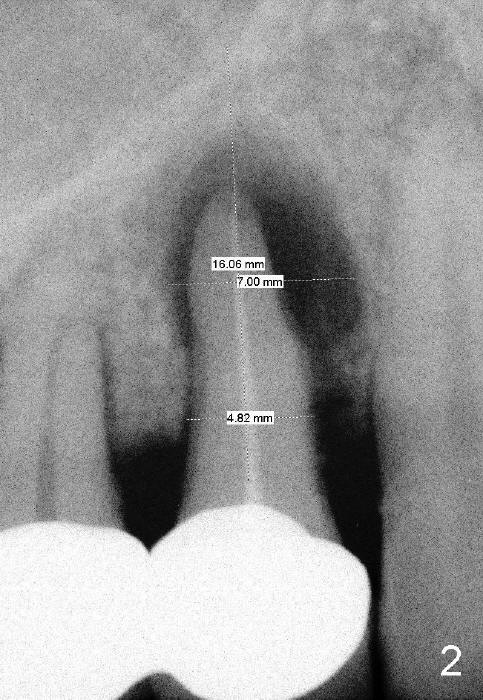

A 57-year-old man refuses treatment for the tooth #5 for 22 months (Fig.1). He suddenly shows up because of severe bleeding from the fistula of the tooth (Fig.2 <). After lengthened discussion, he agrees extraction (Fig.4) and immediate implant (Fig.5-8).

In spite of large periapical radiolucency (Fig.1 *), osteotomy is easier than expected. Use 2 mm pilot drill, 2.5-3.5 mm reamers from 14 mm (bottom of the socket) to 17 mm (sinus floor). The initial point for osteotomy at the bottom of the socket is easy to establish, because it is flat. By the time 5x20 mm tap is inserted, it is palatal (Fig.5). It is mandatory because the buccal plate has been perforated. The tap has to be inserted deeper (from 17 mm to 20 mm, Fig.6) to achieve stability. Insertion torque of 5x20 mm implant (Fig.7 I) is > 60 Ncm. The implant remains palatal so that there is space for bone graft (Fig.8 *). But the bone graft is a little over packed; there is no room to place collagen dressing. The latter will be dislodged and bone graft will be lost if perio dressing is loose prematurely. The perio dressing may have to be re-applied. Depth of bone graft is deemed sufficient if the implant threads are covered. Maximum will be on the rough surface. Physiologically, bone does not extend to the gingival margin.